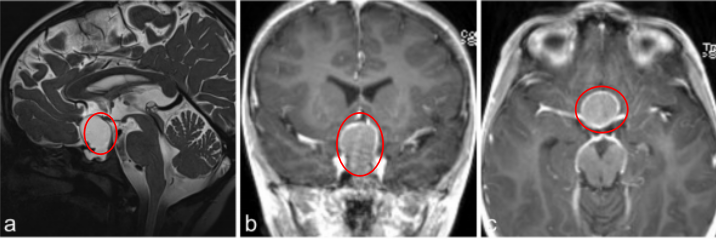

7岁男孩出现垂体功能减退的症状,如体重减轻、生长发育停滞、身体状况不佳和疲劳。就诊四周前,他一直抱怨头痛和呕吐,评估表明是全垂体功能减退。

a–c图MR成像显示囊性病变对比增强,高度怀疑颅咽管瘤

j、k、l图显示,肿瘤得到全切,术后2年没有复发,目前孩子在接受激素替代疗法